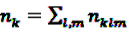

denote the number of prescriptions of drug i with a subsequent event j in the time-window t,

denote the number of prescriptions of drug i with a subsequent event j in the time-window t,  the number of prescriptions to any drug with a subsequent event j in time-window t,

the number of prescriptions to any drug with a subsequent event j in time-window t,  the number of prescription of drug i and any subsequent event in time period t, and

the number of prescription of drug i and any subsequent event in time period t, and  the number of any prescription, followed by any event in time period t. Then the IC, defined in Equation 7, for the time window t can be estimated as

the number of any prescription, followed by any event in time period t. Then the IC, defined in Equation 7, for the time window t can be estimated as